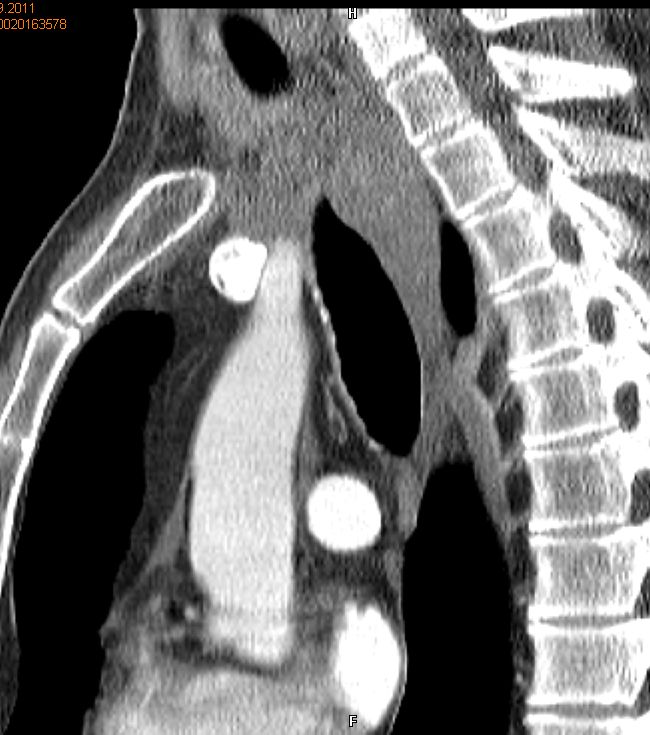

Rezidiv nach Radiochemotherapie eines kleinzelligen Tracheakarzinoms mit großer supraclavikulärer Metastase | |||